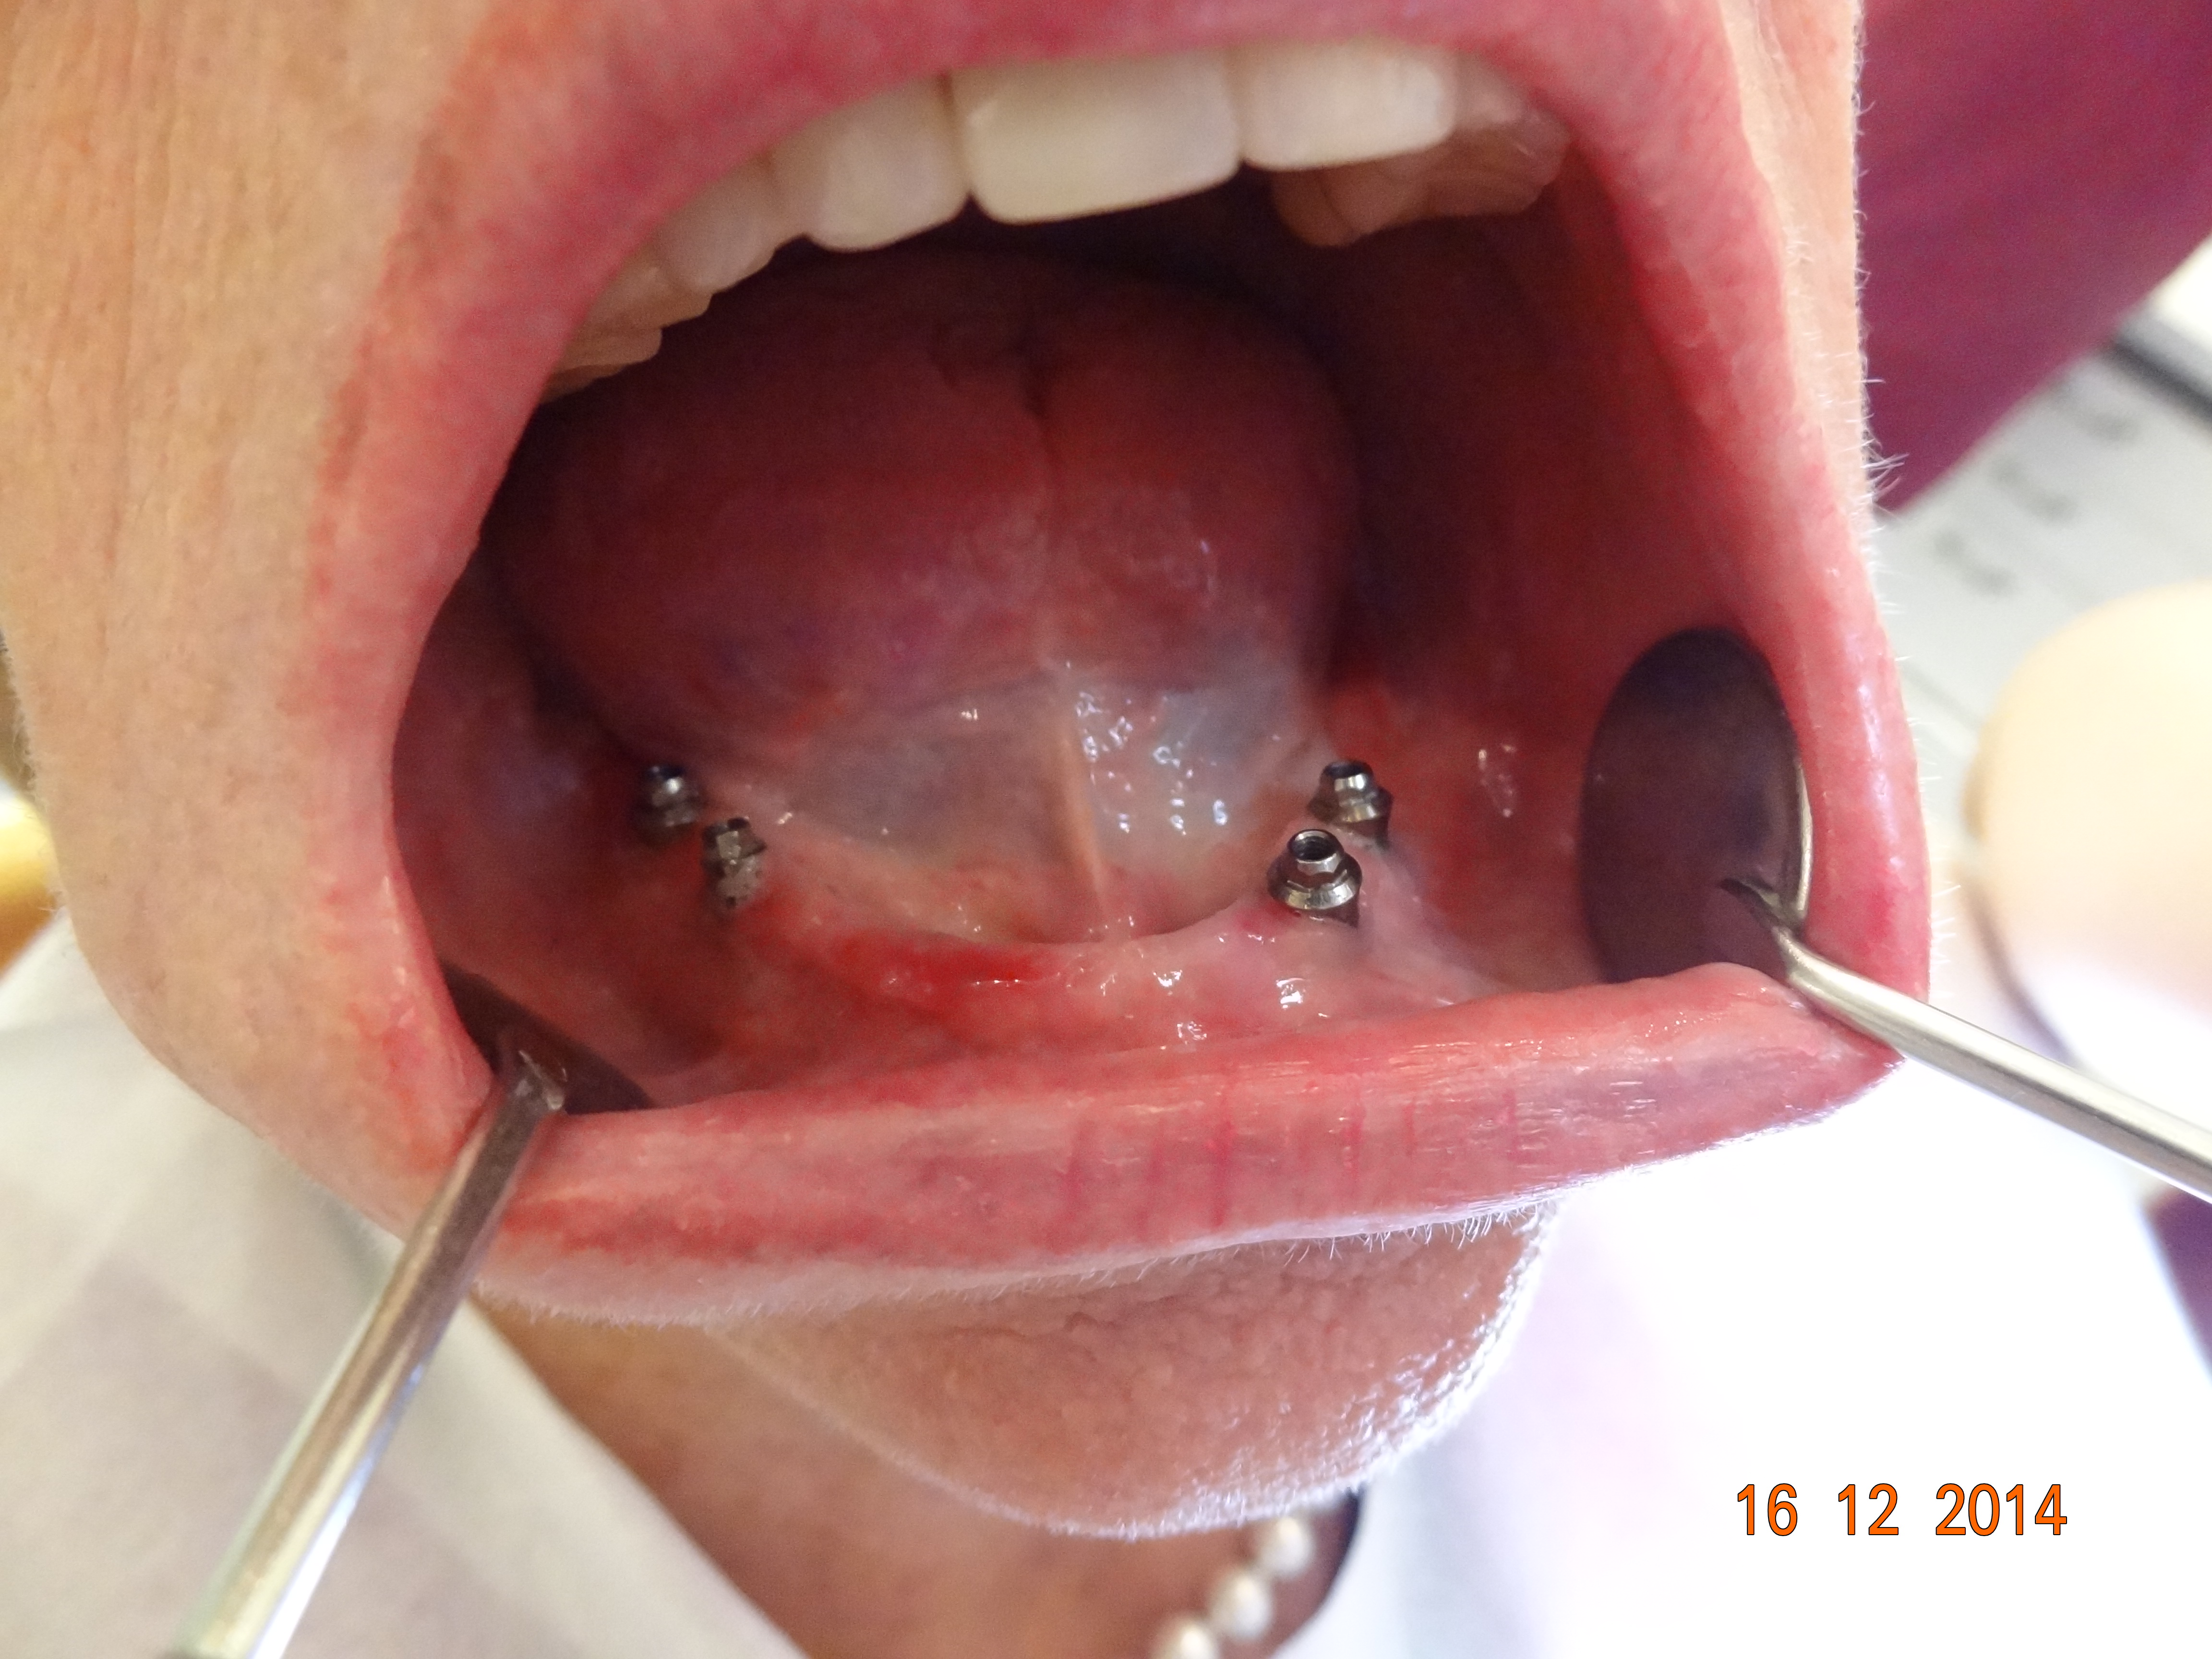

Abbildungen rechts : Eine steggetragene , bedingt abnehmbare Versorgung auf 3 Implantaten im Unterkiefer :